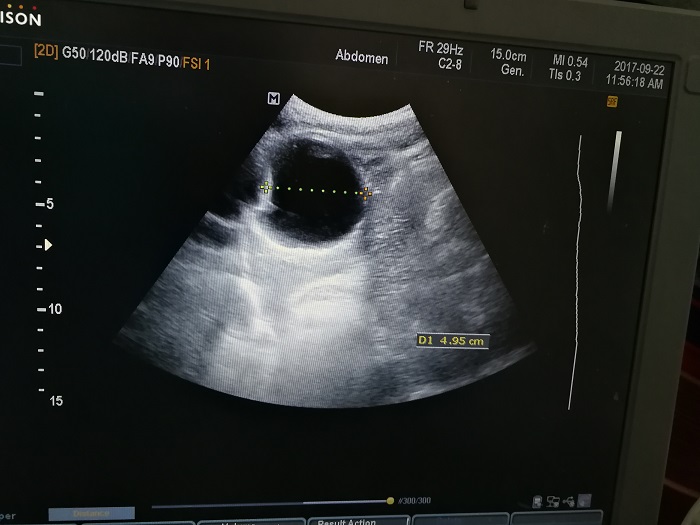

扎西(化名),男,15歲,包蟲病篩查陽性,牧區(qū)孩子,家里有牦牛20頭、羊200只,狗1條,牛羊自家屠宰,飲用河水。

●革吉縣初級(jí)中學(xué)篩查點(diǎn) · B超現(xiàn)場(chǎng)圖片

除了包蟲病篩查外,連續(xù)三天的學(xué)校體檢我醫(yī)療隊(duì)發(fā)現(xiàn)腎積水、腎囊腫、腎結(jié)石的學(xué)生患者較多,我們將體檢到的相關(guān)臟器疾病同時(shí)間反饋給了班主任,讓他們密切觀察病情,及時(shí)通知家長(zhǎng)。劉冬梅醫(yī)生建議,學(xué)校要組織學(xué)生多飲水,同時(shí)多加觀察本地水質(zhì)情況。